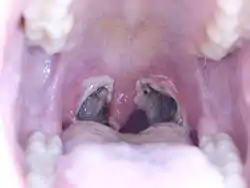

| Typical appearance of the back of the throat three days post tonsillectomy. | |